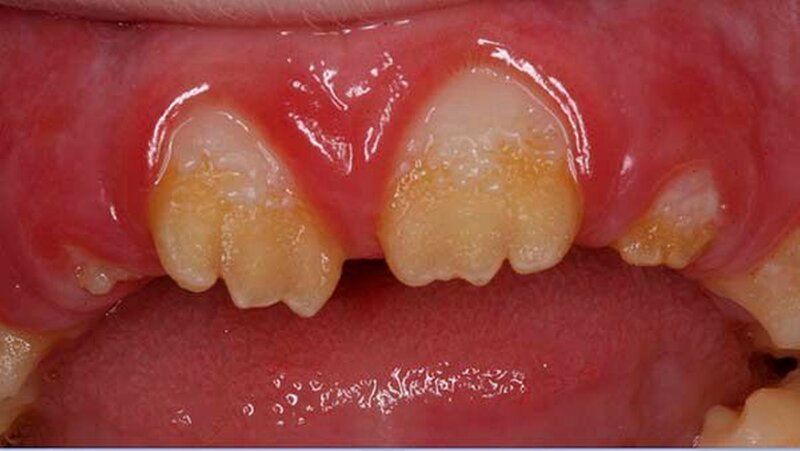

Der zehn Jahre alte Junge stellte sich an der Klinik wegen Schmerzen im ganzen Mund vor. Zusätzlich klagte der Patient über die eingeschränkte Möglichkeit Speisen ab zu beißen (Abbildung 1a und Abbildungen 3a und 3b). Die Familienanamnese ergab eine nahe verwandtschaftliche Verheiratung in der Familie. Das dentale Erscheinungsbild konnte von den Eltern des Patienten in der Verwandtschaft jedoch ausgeschlossen werden.

Der klinische Befund zeigte an beiden Dentitionen eine rauhe, zum Teil verminderte, bis fehlende Schmelzdicke und eine teilweise bräunliche Zahnverfärbung. Letztere wurden auch durch exogene Pigmenteinlagerung verursacht (Abbildung 1b und Abbildung 2).